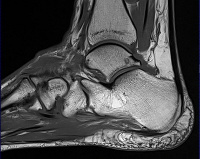

MRI of the ankle joint.

МРТ голеностопного сустава. Развертка слоя за слоем голеностопного сустава основана на фиксации изменений, происходящих в клетках организма под воздействием электромагнитных волн в постоянном магнитном поле. Он используется для диагностики воспалительных процессов, структурных нарушений, травматических повреждений и разрушения тканей в области голеностопного сустава. Это позволяет выявить патологические процессы и поражения в окружающих костях, суставах, связках и мягких тканях. Может быть использовано при подготовке пациентов к артроскопии. Иногда это требует использования контрастного вещества.

МРТ голеностопного сустава используется в диагностике с 1970-х годов на основе клеточного отклика на электромагнитные волны в мощном магнитном поле. Реакция клеток фиксируется специальными датчиками. В серии диагностических исследований МРТ является наиболее высокоточным методом, его назначают при недостаточно информативной рентгенографии и КТ голеностопного сустава. В отличие от методов лучевой диагностики, МРТ позволяет визуализировать не только костную основу, но и окружающие мягкие ткани, которые не отображаются на рентгеновских снимках. Способ не предполагает облучения, поэтому процедуру можно проводить многократно.